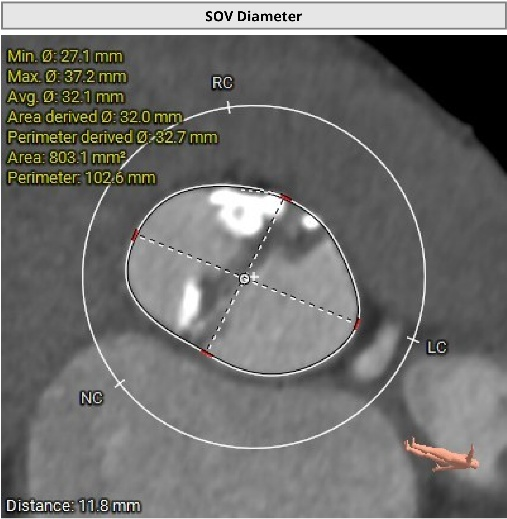

近日,昆山市中医医院心内科团队又成功为一名82岁高龄患者实施经导管主动脉瓣置换术。该患者主动脉瓣口面积仅0.2cm²,而正常成人主动脉瓣口面积一般约为3至4cm²。与此同时,患者还合并重度钙化的二叶式主动脉瓣、轻中度反流,左心室腔径偏小,并有帕金森病病史。多重高危因素叠加,意味着术中导丝跨瓣难度大,循环波动耐受差,整体风险很高。

进一步评估显示,患者瓣膜狭窄程度重,瓣叶钙化明显,左心室腔径偏小,手术中对器械通过、瓣膜释放以及循环稳定性的要求都更高。团队结合术前影像和整体身体状况,制定了周密的介入治疗方案,并做好相关风险预案。

CT评估

瓣膜评估